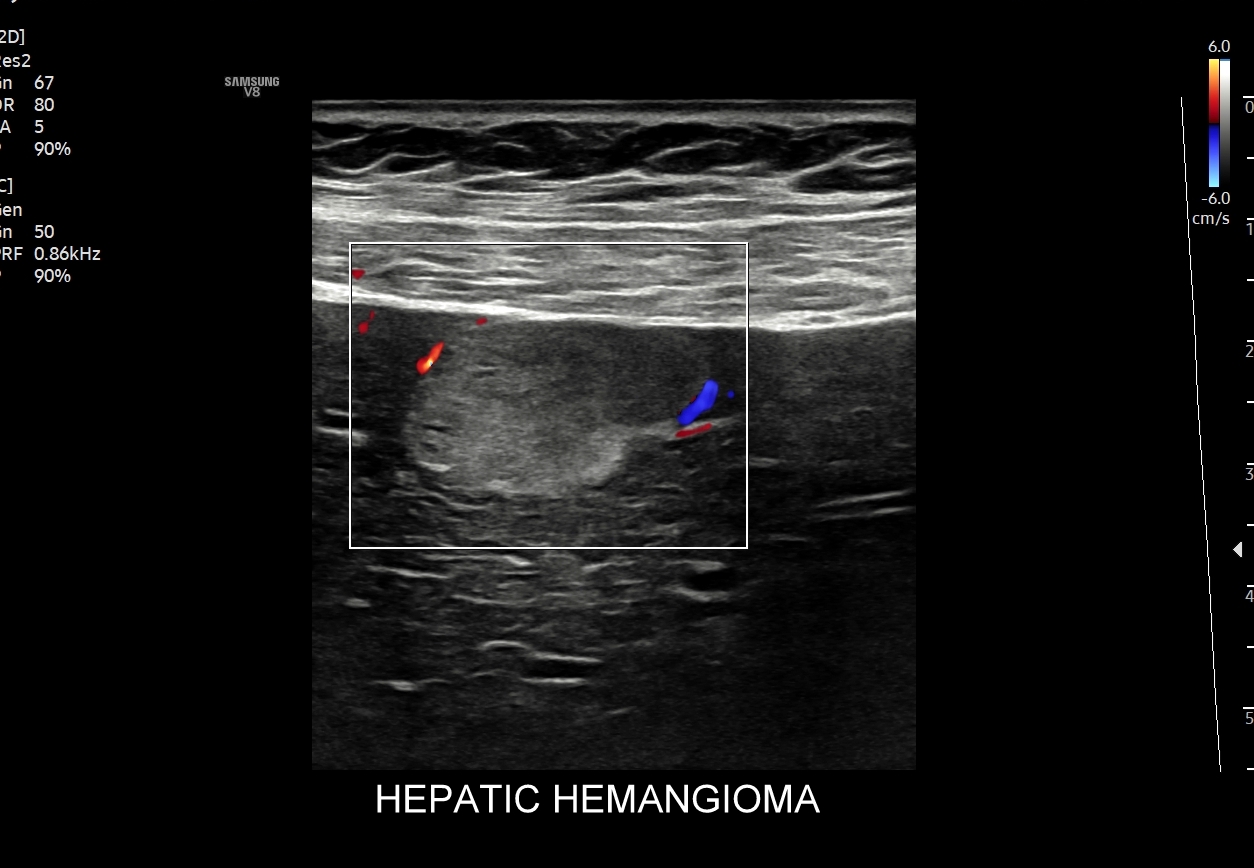

W badaniu USG w prezentacji B w niestłuszczonej wątrobie typowy naczyniak włośniczkowy lokalizuje się w pobliżu gałęzi żyły wątrobowej, a prezentuje się jako ostrookonturowana, hyperechogenna, jednorodna, krągła lub owalna zmiana ogniskowa. Ze względu na niską prędkość przepływu krwi i wynikające z tego ograniczenie detekcji w trybie color-Doppler w naczyniaku nie rejestruje się sygnału. Z kolei w trybie mikrounaczynienia (MVI / MVF) w zależności od czułości aparatury w naczyniaku można zaobserwować delikatny sygnał w postaci „poprószonego śniegu”.

W przypadku zarejestrowania w obrębie hyperechogennej zmiany ogniskowej wątroby w trybie kolorowego Dopplera lub Dopplera mocy (ang. power Doppler) drobnego naczynia lub naczyń, w szczególności krętych i o nieregularnym przebiegu, należy brać pod uwagę prawdopodobieństwo obecności złośliwej zmiany metastatycznej lub innego rodzaju zmiany ogniskowej.